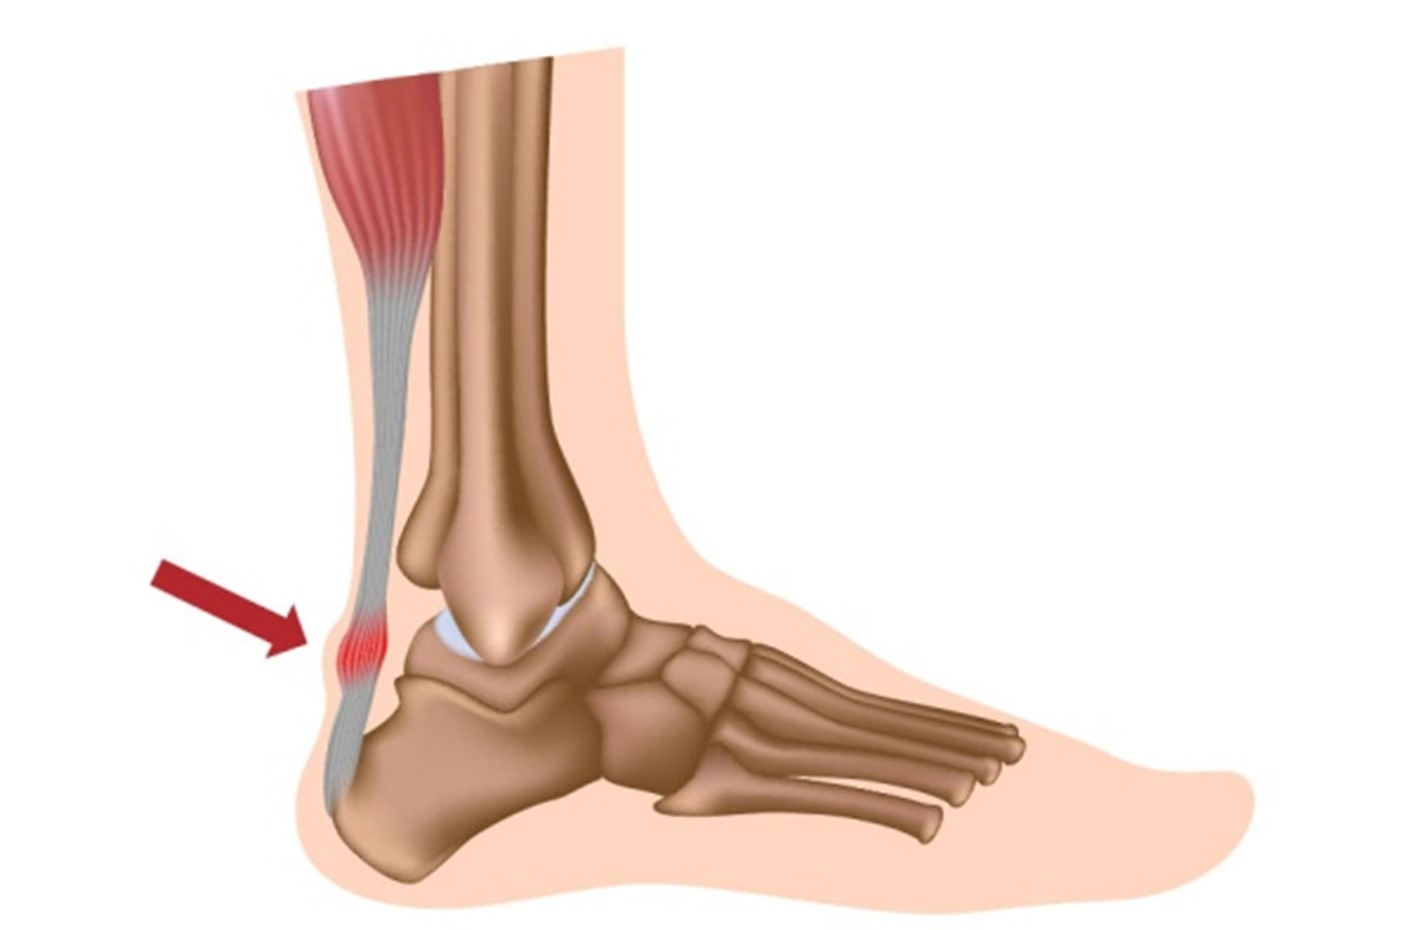

Με τον όρο τενοντίτιδα ή τενοντοπάθεια του Αχιλλείου τένοντα αναφερόμαστε στην άσηπτη φλεγμονή του. Ανατομικά ο αχίλλειος τένοντας βρίσκεται στο πίσω μέρος του ποδιού και καταφύεται στο οστό της πτέρνας ενώ αποτελεί τον ισχυρότερο τένοντα στο ανθρώπινο σώμα. Είναι βασικός τένοντας συμμετέχοντας στη βάδιση και το τρέξιμο προκαλώντας ανύψωση και στήριξη του ποδιού.

Η τενοντίτιδα του αχιλλείου προκαλεί πόνο, δυσκαμψία και οίδημα της προσβεβλημένης περιοχής κάνοντας δυσχερή τη βάδιση και την αθλητική δραστηριότητα. Μπορεί να εμφανιστεί είτε στο σημείο που ενώνεται ο τένοντας με την πτέρνα είτε κεντρικότερα αυτής.

Η διάγνωση τίθεται κλινικά από τον Ορθοπαιδικό με βάση τα συμπτώματα, το ιστορικό και την κλινική εξέταση. Απεικονιστικά θα επιβεβαιωθεί με τη μαγνητική τομογραφία στην οποία θα φανούν τα χαρακτηριστικά ευρήματα της τενοντοπάθειας.